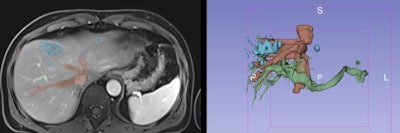

3D models that combine vascular and biliary anatomy using different imaging techniques can contribute to more rigorous planning of complex liver operations, including hepatic resections, living-donor transplantation, vascular intervention procedures, and biliary reconstruction surgery, Portuguese researchers reported at RSNA 2020.

3D models are increasingly used to help surgeons, guiding them through the complex hepatic vasculobiliary anatomy. They can help in the resection of hepatic primary tumors and metastasis because they can demonstrate the location within hepatic segments and the relationship with adjacent structures such as hepatic and portal veins, arteries, and bile ducts.

3D models are useful in surgical planning, and optimal resection planes can be selected prior to surgery. In patients at risk of post-hepatectomy liver failure, liver volumes may be calculated for various possible resection approaches.